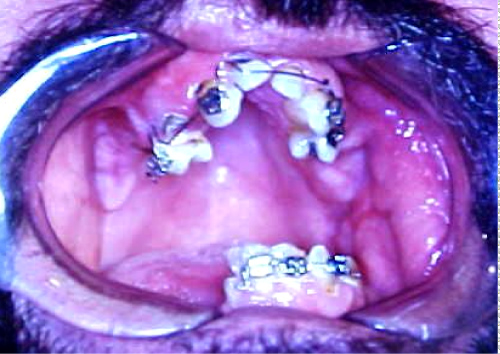

A thirty-seven-year-old male patient presented to the Oral and Maxillofacial Clinic of "Evangelismos" Hospital complaining of the inability to open his mouth since his birth. When the medical history was received, it was found that the unilateral TMJ ankylosis was of congenital etiology due to the operative instrumental delivery. The patient had undergone corrective surgery before years, but the ankylosis had relapsed. During the clinical examination the maximum opening of the mouth was 2-3 mm, while the lateral movements of the mandible were depressed. The development of the anterior region of the maxilla was disturbed and formed in a V-shaped dental arch due to the use of a feeding instrument from neonatal age (Figure 1). Α conventional radiographic examination was performed including a panoramic X-ray, as well as a CT and three-dimensional CT scan. Radiological examinations showed that the ankylosis was in the right TMJ due to the development of bone between the condyle and the articular fossa including anterior and posterior articular tubercle (Figure 2).

Figure 1: Limited opening of the mouth and the V-shaped formation of the maxilla. View Figure 1